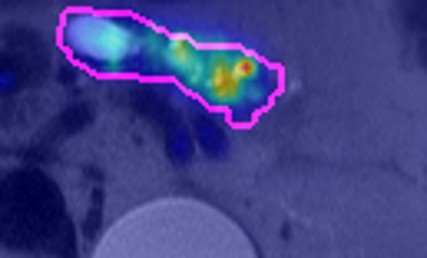

When compared with the visual assessments of three expert radiologists, our models demonstrated superior accuracy in both no/low-risk and high-risk cases. As shown in Table 3, the DenseNet-121 model with probability fusion achieved a no/low-risk classification accuracy of 94.66% and a high-risk accuracy of 47.18%, outperforming the radiologists’ average accuracies of 93.91% and 46.01%, respectively. While this overall performance suggests that Cyst-X surpasses expert-level assessments, a more nuanced interpretation is warranted. Notably, Radiologist 2’s performance demonstrates a tendency toward high Negative Predictive Value (NPV)at the expense of sensitivity (i.e., substantially lower accuracy at just 32.39%), which risks missing malignant cases. In contrast, our model maintained a more balanced performance across risk categories, demonstrating both strong sensitivity and specificity. This balance suggests that Cyst-X is not only more accurate overall but also potentially more reliable in clinical decision-making, where both under- and over-diagnosis carry significant consequences. For visual explainability of classification results, visual saliency-based methods are often used, although most of such methods are not true explanation methods, but show mostly learned patterns in the image region in correlation to the result. For this purpose, GradCAM [selvaraju2017grad] and Information Bottleneck Attribution (IBA) [schulz2020restricting, demir2021information] based visualizations were generated (See Supplementary materials).

To interpret model predictions, we generated visual attribution maps using Grad-CAM [selvaraju2017grad] and IBA [schulz2020restricting, demir2021information]. Grad-CAM highlights spatial regions that strongly influence the model’s decision by computing gradients of the target class score with respect to feature activations. In contrast, IBA offers sharper and more focused explanations by learning a perturbation mask that minimizes mutual information between intermediate representations and predictions, thereby isolating only the most critical features for decision-making. Visualizations from both methods are provided in the Supplementary Materials.